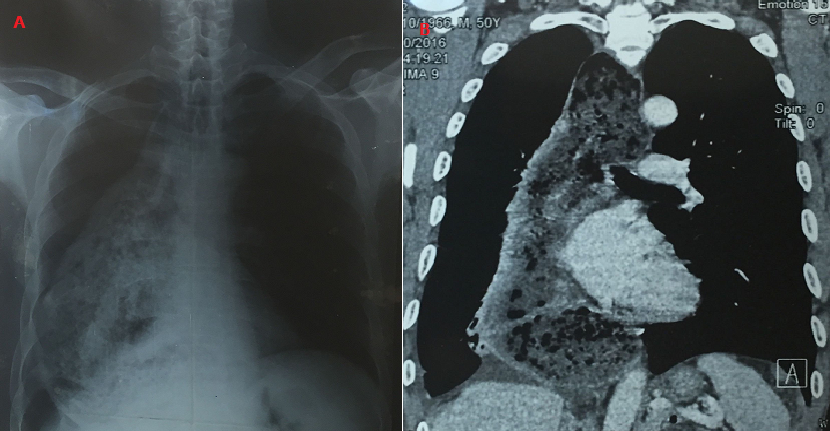

Il s'agit d'un homme de 65 ans, non alcoolo-tabagique, aux antécédents médicaux de reflux gastro-œsophagien pour lequel il n'a jamais consulté. Il est admis au service de pneumologie pour l'exploration d'une toux quinteuse sèche, insomniante, associée à une douleur thoracique droite diffuse à type de pesanteur évoluant depuis 1 mois environ dans un contexte de fièvre vespéro-nocturne sans perte de poids. Les examens clinique et radiologique avaient retrouvé un syndrome d'épanchement liquidien pleural droit. La radiographie de contrôle réalisée après la ponction pleurale évacuatrice, avait mis en évidence une opacité inhomogène occupant la quasi-totalité du champ pulmonaire droit (A). Le scanner thoracique était en faveur d'un mégaœsophage thoracique associé à une pleuro-pneumopathie non spécifique (B). Le patient a bénéficié d'une endoscopie digestive haute qui n'avait pas retrouvé de signe suspect de cancer. L'évolution de la pleuro-pneumopathie était favorable après un traitement par amoxicilline.